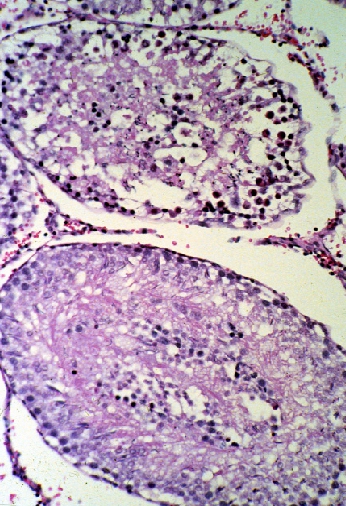

Forty rats, in groups of ten, were orally dosed with corn oil, corn oil and 2,000 mg/kg trichloroethylene (TCE), corn oil and 2,000 mg/kg lead carbonate, or a mixture of 2,000 mg/kg each TCE and lead carbonate, in an effort to determine whether or not dual administration of both TCE and lead would have an additive effect on neurotoxicity and overall health as indicated by behavioral and physiologic measurements and tissue pathology. A functional observational test battery (FOB) was performed before, during, and after dose administration to assess dose-related changes. The FOB testing assessed behavioral and physiologic measurements such as gait, open field activity, posture, grip strength, and handling reactivity. Pathological examination included assessing dosing related changes in the testis, spleen, heart, liver, kidney-adrenals, and brain.

Results indicated that each compound was toxic individually, and that the combination of the two neurotoxicants provided conflicting indications of both reduced and additive toxicity. The toxicity of lead carbonate caused the vast majority of toxic consequences in the study. A reduction in body weight and an increased resistance to cage removal were the only statistically significant changes observed in the FOB that were due to concurrent administration of lead and TCE. Organ-to-body weight and organ-to-brain weight calculations showed evidence of a statistical difference between the lead and lead/TCE dosed animals for liver, kidney-adrenals, and body weight. The significance of these changes is not fully understood.